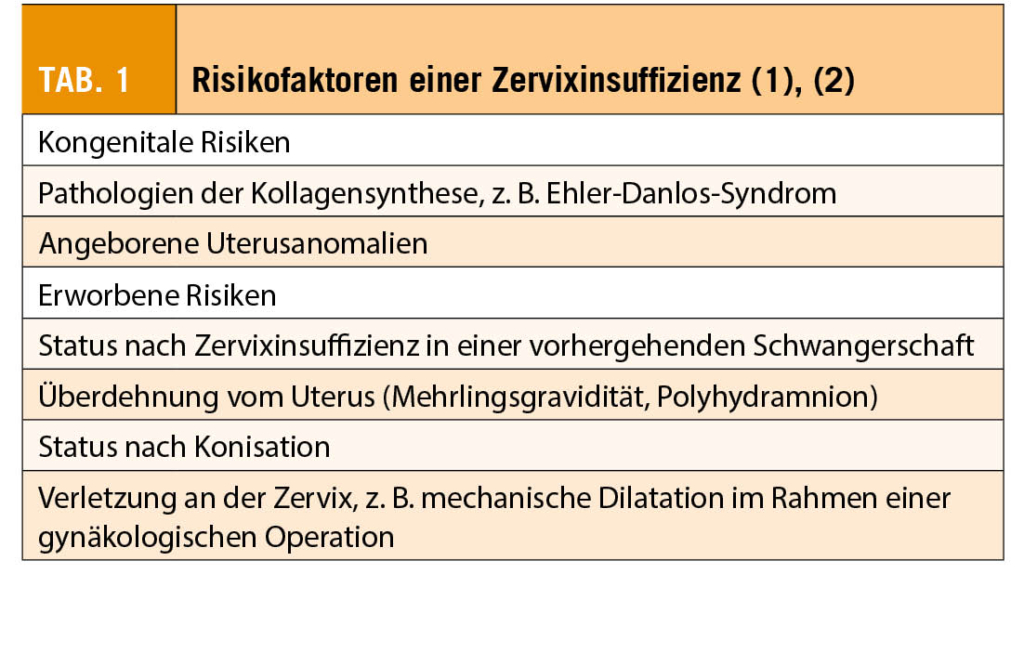

Die Risikofaktoren für eine Zervixinsuffizienz können entweder kongenital oder erworben sein (Tab.1). Eine familiäre Häufung konnte nur in einer Studie beobachtet werden. Die Kenntnis der Risikofaktoren ist hilfreich für die frühzeitige Erkennung einer Zervixinsuffizienz. Gleichzeitig ist die Abgrenzung einer vorzeitigen Wehentätigkeit für die weitere Behandlung von Bedeutung.